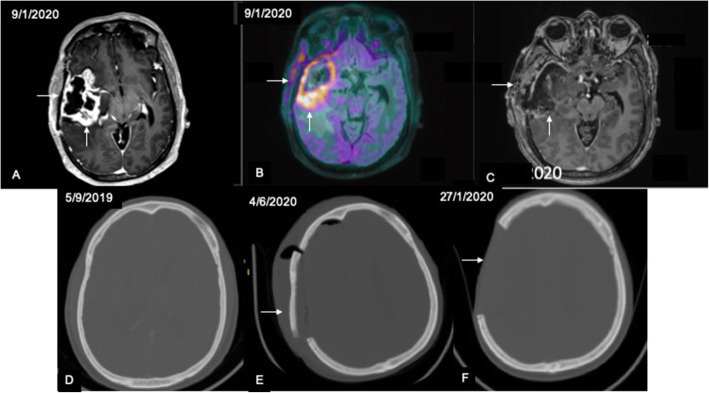

Molecular imaging is a useful adjunct to advanced MRI in identifying recurrence in post-treatment gliomas. Most of the PET studies have been performed using 18-fluoro-deoxyglucose (FDG) as the radiotracer. Although some studies reported a low specificity for FDG-PET in detecting recurrence (Ricci et al., 1998; Hustinx et al., 2005), a meta-analysis by Wang et al. (Wang et al., 2015) revealed diagnostic performance comparable to magnetic resonance spectroscopy (MRS). In this metanalysis comparing FDG-PET, C-11 methionine PET, and MRS, the pooled sensitivity for FDG-PET was the lowest at 70% and the specificity was highest at 88% (Wang et al., 2015). The heterogeneity in data related to FDG-PET and lower sensitivity may partly be attributed to the uptake of FDG by the normal brain parenchyma which leads to misdiagnosis in some cases (Soni et al., 2020). In this regard, amino acid tracers such as C-11 Methionine have a distinct advantage in that the background normal parenchymal uptake is much less thus leading to a higher tumor to background ratio and has shown promising results in various studies (Takenaka et al., 2014; Kim et al., 2010; Deuschl et al., 2018; Minamimoto et al., 2015; Terakawa et al., 2008). In our study, the highest AUC and highest diagnostic accuracy were obtained for TBRmax with a sensitivity slightly less than that of rCBV ratio (81.8 vs. 84.8%) and a much higher specificity (92.3 vs. 76.9%) using a threshold of 1.23. These results are comparable to those of other studies which have reported sensitivity and specificity ranging between 66–91 and 60–100% respectively for differentiating recurrent lesion from treatment related changes (Takenaka et al., 2014; Kim et al., 2010; Deuschl et al., 2018; Minamimoto et al., 2015; Terakawa et al., 2008). A metanalysis (Nihashi et al., 2013) revealed pooled sensitivity of 70% and specificity of 93% for detection of recurrence in high grade gliomas using C11-methionine PET which is comparable to the values obtained in this study. Besides, we also observed that visual analysis of PET images for recurrence showed the highest agreement with the final diagnosis compared to that of MR perfusion and diffusion. This is expected in view of the increased contrast between lesion uptake and brain parenchyma even in lesions located close to the cortex. Our findings are corroborated by another study (Minamimoto et al., 2015) in which no significant difference was seen between visual and quantitative analysis in differentiating recurrent brain lesions from radiation necrosis on C11-methionine PET. However, one of the important disadvantages of C11-methionine is that uptake may also be seen in areas of radiation necrosis (Fig. 7) and acute inflammatory pathology (Fig. 8) leading to a false positive diagnosis (Ogawa et al., 1991). In view of uptake by inflammatory cells, it has been reported to show lower diagnostic accuracy compared to other amino acid radiotracers like fluroethyltyrosine (FET) and fluoro-dihydroxyphenylalanine (F-DOPA) (Nihashi et al., 2013; Minamimoto et al., 2015; Galldiks et al., n.d.). In this cohort, we encountered a false positive diagnosis in 4 out of 48 cases (8.33%) on methionine PET in which the findings were discordant with MR perfusion and diffusion.

Fig. 8.

Sequence of images showing false positive C11 methionine uptake in acute inflammatory pathology: Axial post-contrast T1 MPRAGE (A) in a case of suspected recurrence shows parenchymal enhancement (vertical arrow) suggestive of recurrent lesion with associated enhancement of the overlying bone and soft tissues (horizontal arrow). C11 methionine PET image fused with axial T1 MPRAGE (B) shows tracer uptake along the bone and soft tissues (horizontal arrow) in addition to parenchymal uptake (vertical arrow). Here the uptake in the bone and soft tissues occurred due to osteomyelitis. Follow-up axial post-contrast T1 MPRAGE following chemo/radiotherapy (C) shows reduction in parenchymal enhancement (vertical arrow) with persistent enhancement in bone and soft tissues (horizontal arrow). Sequential axial CT brain images in bone window (D–F) show initial scan (D) with normal bone followed by progressive osteomyelitis in E and excision of the infected bone in F